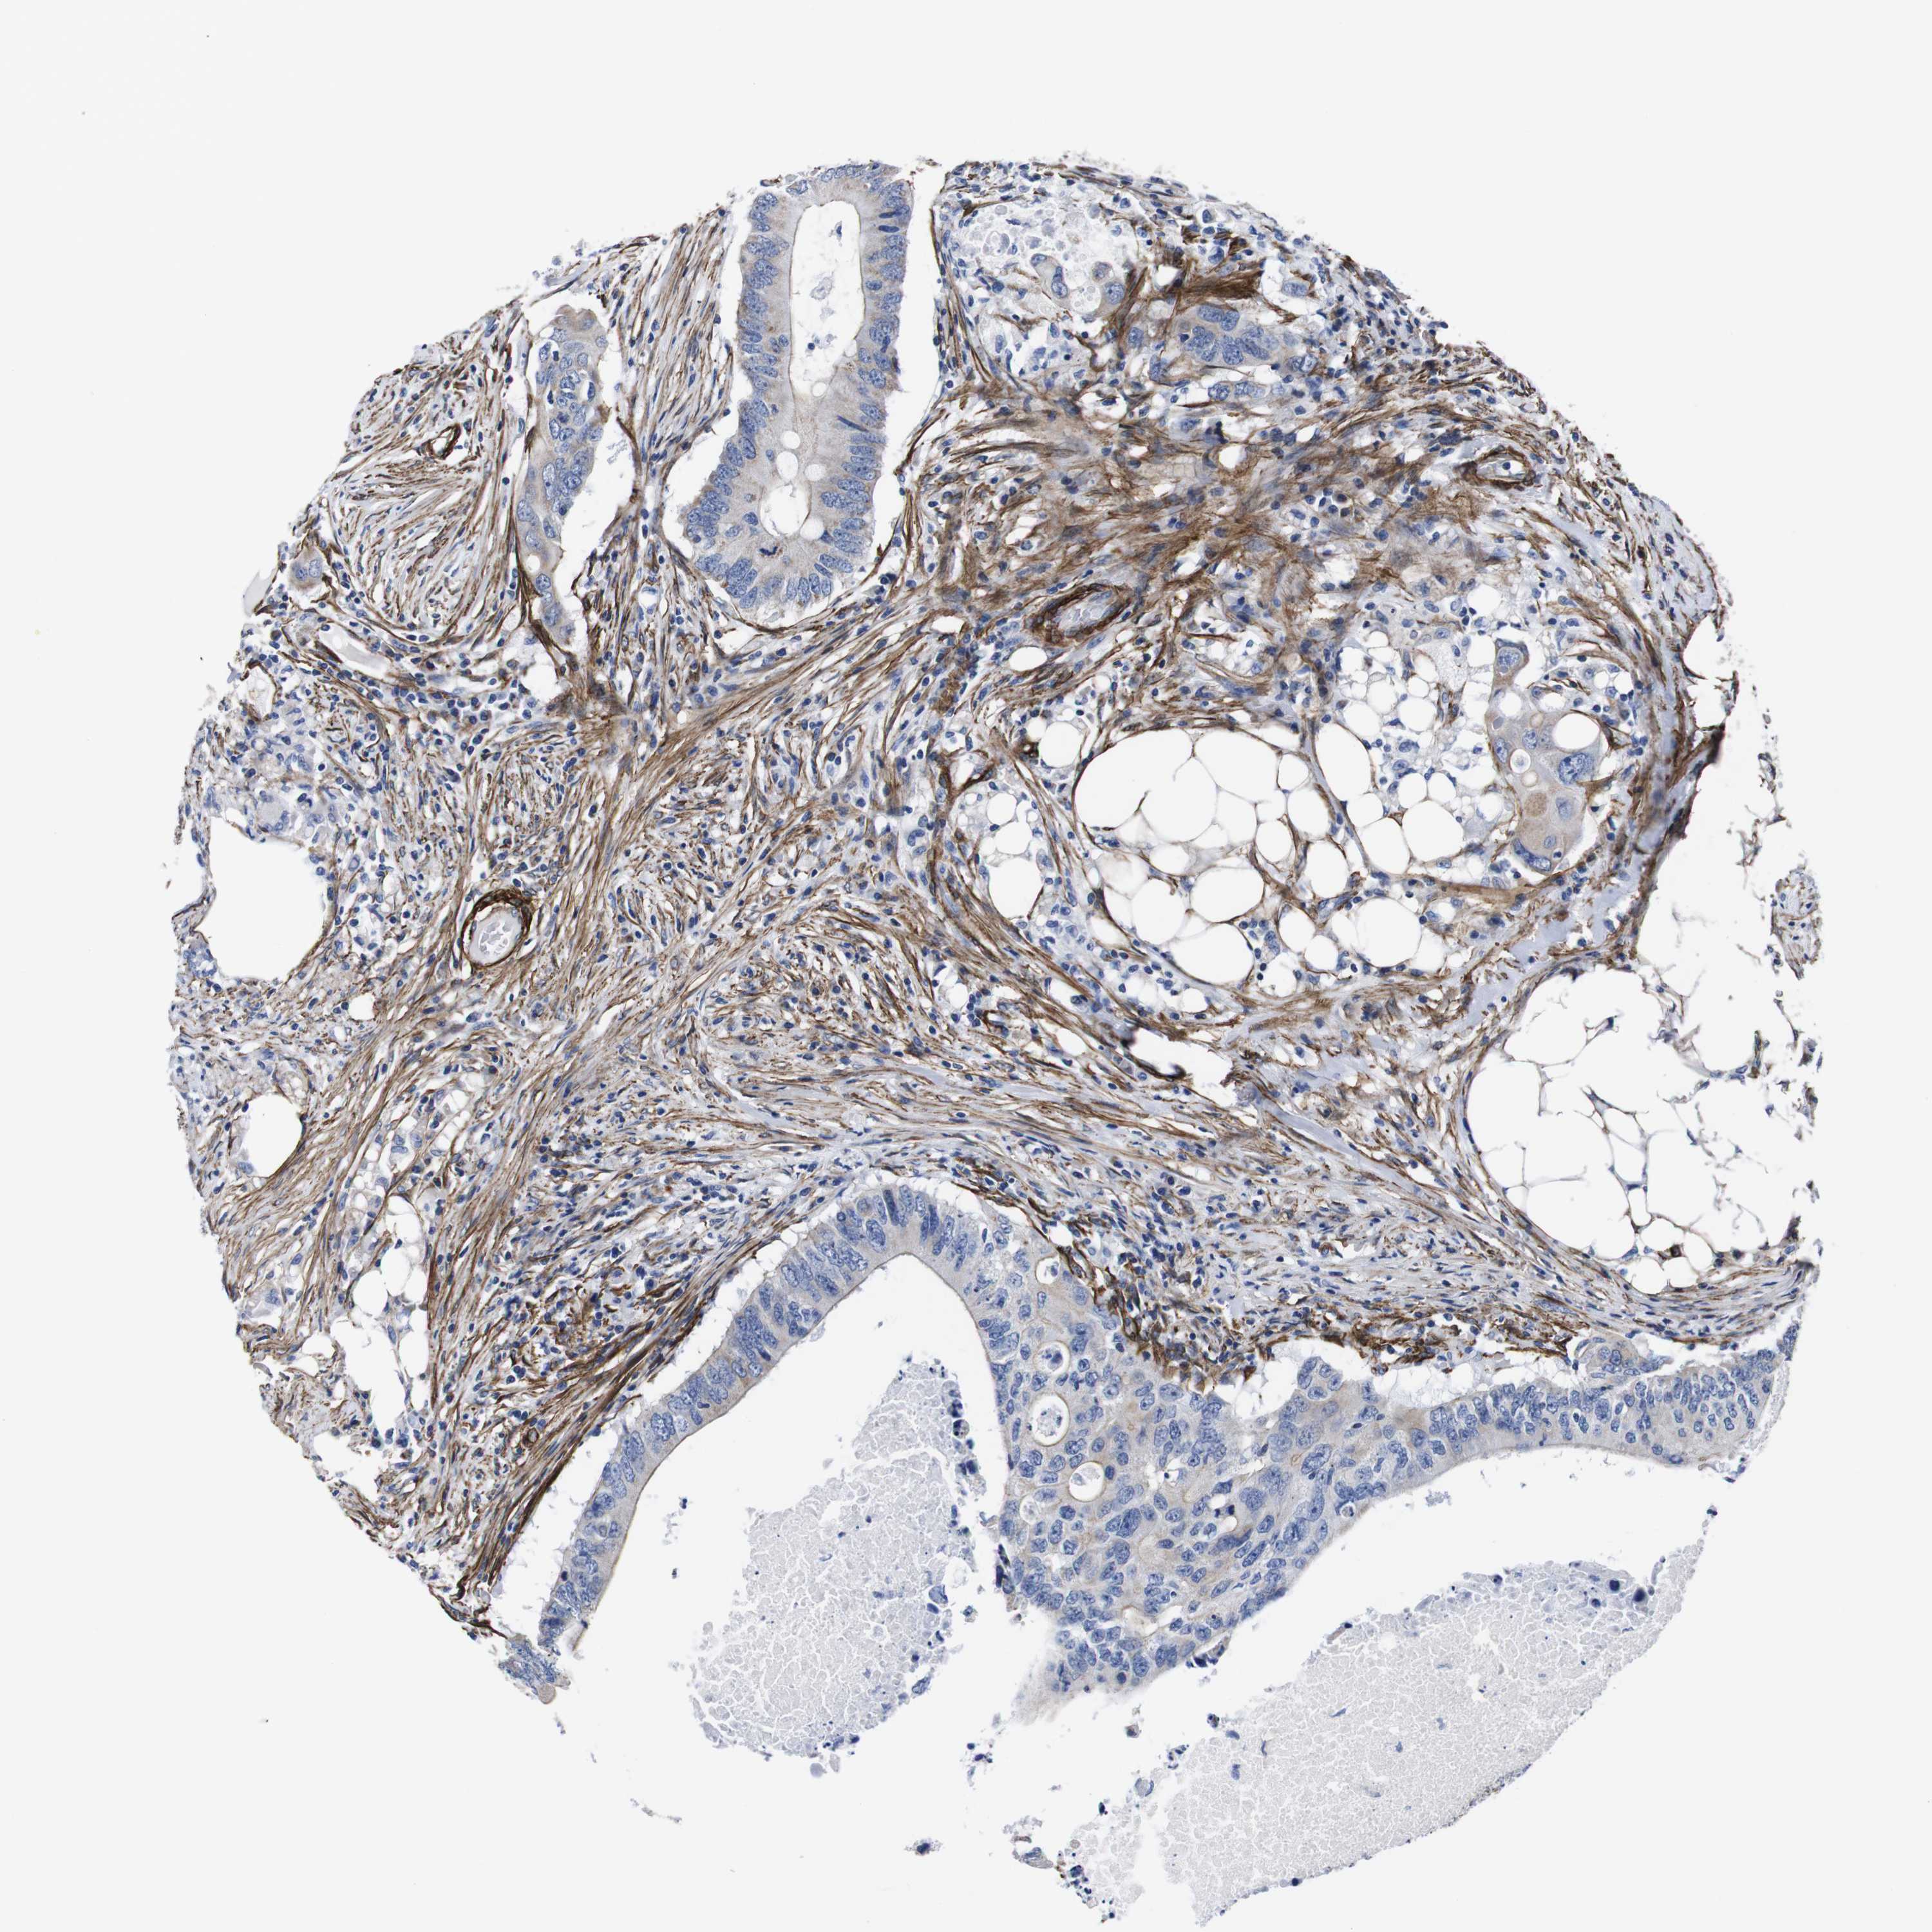

CANCER COLORECTAL CANCER Show tissue menu

Colorectal cancer

Rectum adenocarcinoma